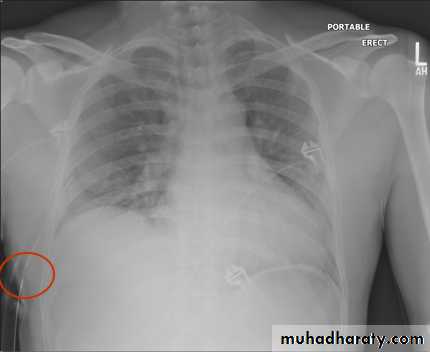

Severe dyspnea with shock